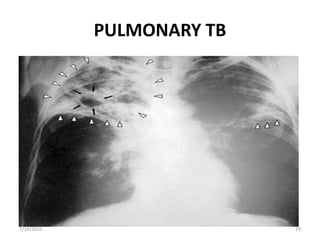

PULMONARY TB

Chest radiography: bilateral

shadows, especially if these are

in lesions in upper lobes- TB